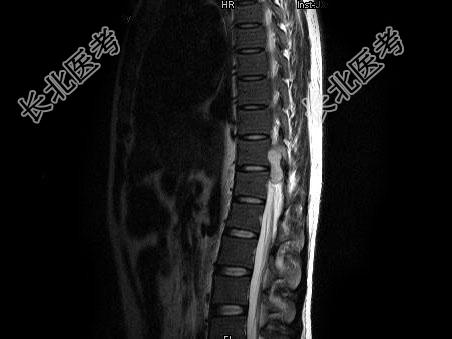

- 单项选择题男,25岁, 慢性腰痛伴间歇性跌倒半年,双下肢无力不能行走1月, MRI见下胸段椎管内肿瘤呈“哑铃”状应诊断为 ( )